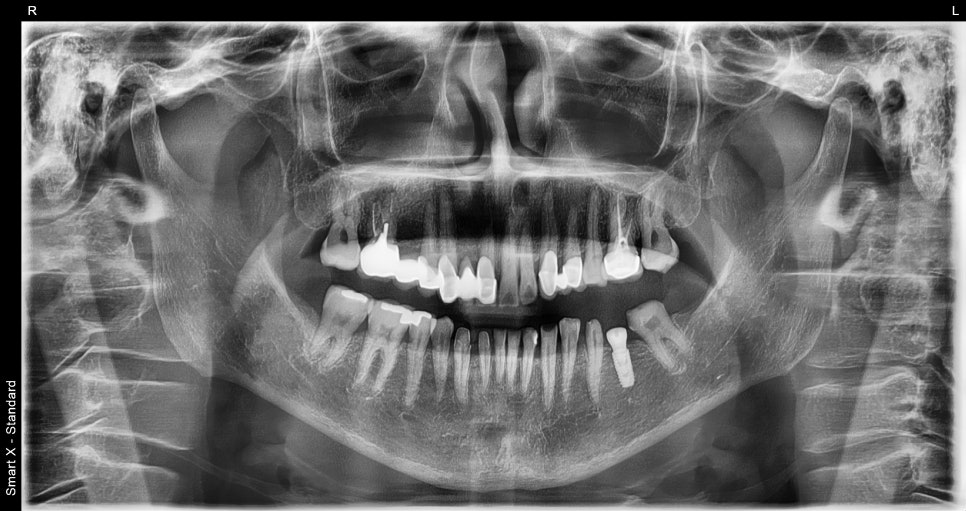

최종 파노라마 X-ray

임플란트 수술 직후 촬영한 X-ray입니다.

수술 직후 파노라마 X-ray

➤ 치료 마무리 사진

어금니 부위에 임플란트를 식립한 후, 크라운까지 셋팅이 완료된 모습입니다. 자연치와 조화로운 색상과 형태로 기능과 심미성을 동시에 회복했습니다.